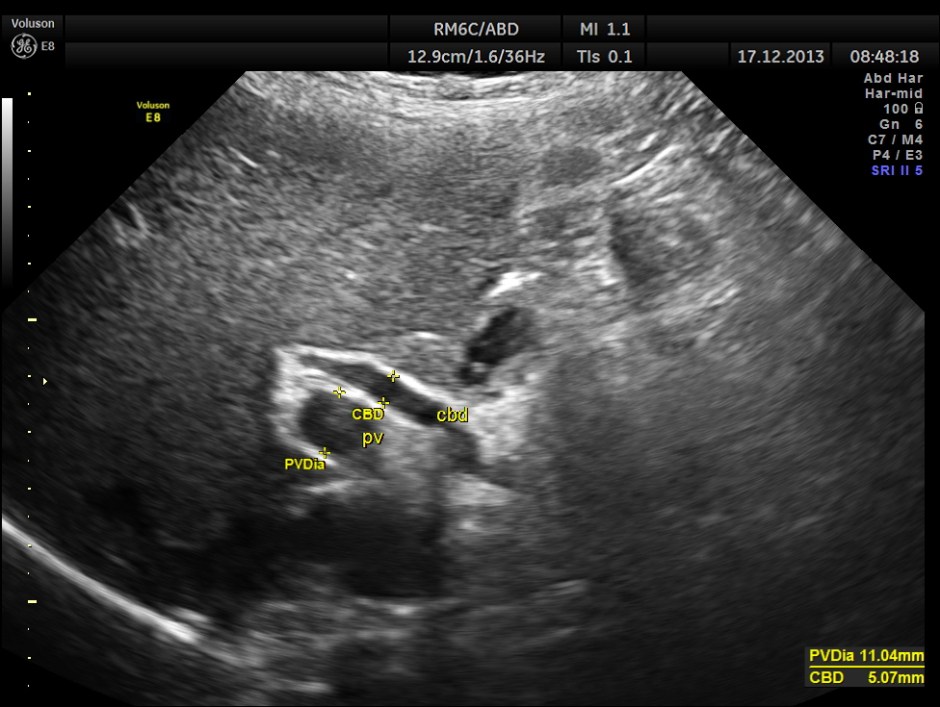

This was a 63-year-old gentleman who came for recurrent episodic right upper quadrant pain of 2 to 3 weeks duration.On examination Murphy’s sign was positive. The pictures follow.

ACUTE CHOLECYSTITIS WITH MULTIPLE SMALL GALLSTONES AND ECHOGENIC SLUDGE WAS SEEN.

The Common Bile Duct is 5.07 mms.

Now a quick question . What is the normal range of measurement of the C.B.D. ?

a small although statistically significant increase in the caliber of the common bile duct with increasing

age (60 years old or less, mean diameter 3.6 mm ± 0.2mm, versus over 85 years old, mean diameter 4

mm ± 0.2 mm, P = 0.009). Although the common bile duct did increase in size with aging, 98% of all

ducts remained below 6 to 7 mm, the commonly accepted upper range of normal.